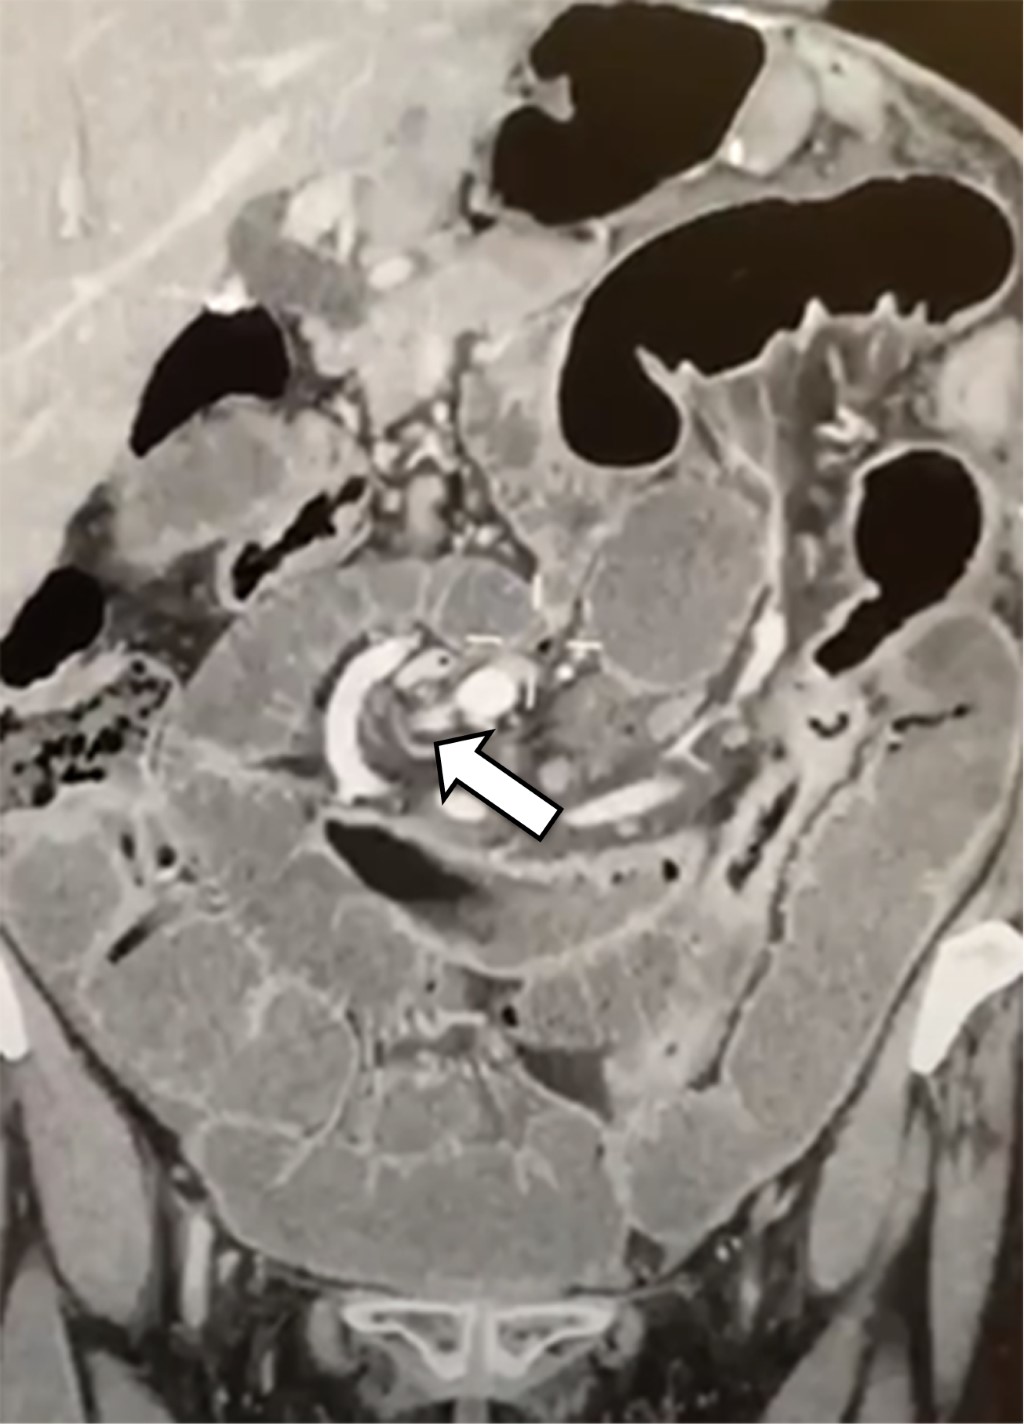

Petersen's hernia after gastric mini-bypass, an unusual situation

The one anastomosis gastric bypass or mini-gastric bypass is a bariatric procedure that has gained popularity in recent years, with efficacy and safety comparable to Roux-en-Y gastric bypass. Petersen's hernia after mini-gastric bypass is a rare complication, so there is not consensus on its routine closure. There are few reported cases, most of them being an incidental intraoperative finding after a picture of chronic abdominal pain, persistent biliary gastroesophageal reflux, or intestinal occlusion. We present the case of a 58-year-old female with a history of mini-gastric bypass 10 years previously with intestinal occlusion and a Petersen hernia with segmental intestinal ischemia, meriting resection and intestinal anastomosis and a conversion to Roux-en-Y gastric bypass with closure of mesenteric defects.

Figure 1

Figure 2

Figure 3

Figure 4